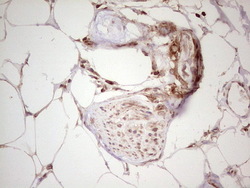

- Main image

- Experimental details

- Immunohistochemical staining of paraffin-embedded Human Ovary tissue within the normal limits using anti-WIBG mouse monoclonal antibody. (Heat-induced epitope retrieval by 1 mM EDTA in 10mM Tris, pH8.5, 120C for 3min, TA806496)

- Validation comment

- IHC